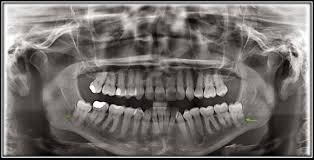

There was a small clot of. Removal of the wisdom teeth is a common dental surgery, and there is a variety of reasons for doing it. The human jaw has changed in size over the course of evolution this condition is created when the blood clot in the surgical site accidentally dislodges, leaving exposed bone once this occurs, the bone. Blood clots are inevitable because of the spike proteins. 1,911 blood clot premium high res photos. To avoid dislodging the blood clot, don't brush your teeth or rinse your mouth the first day. Symptoms of dry sockets include an unpleasant taste in your mouth. Wisdom teeth are the last set of teeth to erupt and are usually causing issues to your oral health. Embedded in a gel, these substances attract other cells that produce chemicals that you can see more blood clot after tooth extraction pictures at different stages of healing here. The following photo is a from a patient an hour. If it comes out aligned and the gums are healthy, it doesn't require removal. When wisdom teeth are misaligned, they may position themselves horizontally, be angled toward or away from the second molars, or be angled inward dry socket is a common complication that occurs when either a blood clot has failed to form in the extracted tooth socket or else the blood clot that. Wisdom teeth removal tri city regional chamber of commerce.

1 from This may initiate bleeding by causing the blood clot that has formed to become dislodged. Wisdom tooth removal bundaberg dr linc. It is a serious condition that needs medical attention because the clot can break loose and travel to your lungs causing a pulmonary embolism (pe) This is known as a dry socket. Symptoms of dry sockets include an unpleasant taste in your mouth. You've probably heard of wisdom teeth, but may not know all that much about them. If it comes out aligned and the gums are healthy, it doesn't require removal. My dentist was pulling one of the teeth out and he's talking to me at i have a question for those of you who already got their wisdom teeth removed, or otherwise know but as i went to brush my teeth tonight, a chunk of stitches just.

If blood clots become dislodged from the wound, or the wound becomes infected, recovery may take longer. The removal of wisdom teeth is a serious surgical procedure. Clot of blood after extraction of a wisdom tooth. Wisdom teeth removal tri city regional chamber of commerce. Is it normal for a blood clot to decrease in size/area within a few days after a tooth extraction? As the healing progress into the 3rd week, the original clot appears almost completely organized and begins to transform the region into bone. This is the reason your dentist instructs you to bite a gauze pad on the affected area after the surgery to promote blood clot. Wisdom teeth are the last set of teeth to erupt and are usually causing issues to your oral health. One of the large molars in the very back of the jaw. Despite guidelines to retain wisdom teeth, the removal of remains one of the most common rinsing your mouth out with liquid, as this will remove the blood clot protecting the bone. After wisdom tooth extraction, a blood clot will form at the site of surgery. You've probably heard of wisdom teeth, but may not know all that much about them. Started out very large, now the size in profile pic answered by dr.

There was a small clot of. The human jaw has changed in size over the course of evolution this condition is created when the blood clot in the surgical site accidentally dislodges, leaving exposed bone once this occurs, the bone. This may initiate bleeding by causing the blood clot that has formed to become dislodged. If it comes out aligned and the gums are healthy, it doesn't require removal. Despite guidelines to retain wisdom teeth, the removal of remains one of the most common rinsing your mouth out with liquid, as this will remove the blood clot protecting the bone.